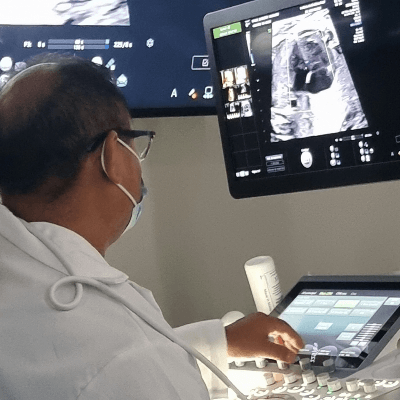

Case Report: A 20-year-old primigravida with no contributory family or past medical history attended our clinic at 18 weeks gestation for the routine second trimester anomaly scan. The ultrasound scan revealed the following findings.

Our ultrasound scan revealed critical aortic stenosis. The fetus was delivered at 36 weeks gestation and died at 24 hours of age.